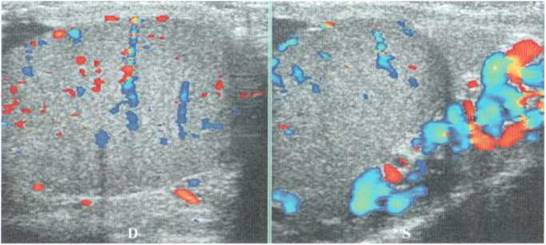

Подростку предлагается лечь на спину. Проводится УЗИ яичек: в режиме двух полей фиксируются оба яичка и измеряются их размеры. Затем оцениваются вены гроздьевидного сплетения, их диаметр в клиностазе (рис. 3.2)

Рис. 3.2. Этап исследования в клиностазе. Измерение размеров яичек (между стрелками с пунктиром) и вен гроздьевидного сплетения (между двойными стрелками)

Фиксируется наличие в венах гроздьевидного сплетения кровотока в клиностазе (3.3).

Рис. 3.3. Этап исследования в клиностазе. Оценка кровотока при спокойном положении пациента